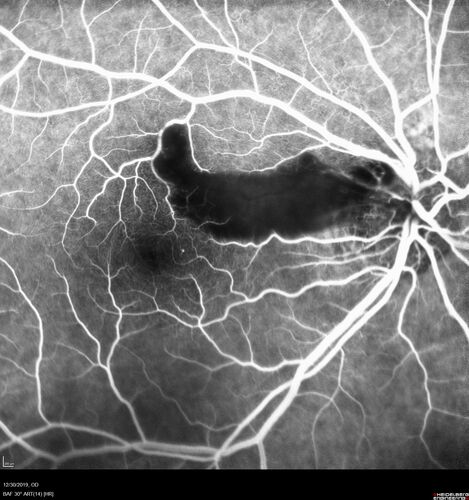

Cilioretinal Artery Occlusion - non central

81 year old female She noticed sudden vision loss in the right eye just before Christmas while watching television.  This was about one week ago.  She noticed when she closed her left eye and looked out of her right eye there was a darkness in the vision.  The left eye is OK.  She has no history of stroke and no neurological problems.  She had a few headaches recently but they went away.

PMHx: HTN, Breast Cancer

Meds: HCTZ, Atorvastatin, Atenolol, Anastrozole

VA 20/80 OD, 20/32 OS

VA improved to 20/40 in one month in the involved eye